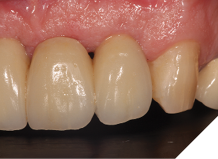

The definitive bridge was fitted and torqued in situ uneventfully after such excellent healing of the provisional bridge (Figs. 31-37).

Fig. 31

Fig. 32

Fig. 33

Fig. 34

Fig. 35

Fig. 36

Fig. 37

Final result

The definitive bridge has integrated well and both hard and soft tissue healing has gone well and very predictably. The chosen biomaterials have integrated well and healed exactly how we would expect them to. The patient was very happy with the aesthetic result especially when we consider what he had been used to preoperatively. The function and phonetics met the patient’s expectations and overall, we were all very happy with the result.